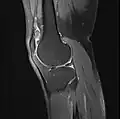

MRI

Both anterior cruciate ligament (ACL) and posterior cruciate ligaments (PCL) are hypointense on both T1 and T2 weighted images of MRI. However, some high signal striations are often seen at the distal part of the ACL, making ACL higher intensity than PCL on MRI scans.[20]

Knee MRI (PD TSE FS sagittal)